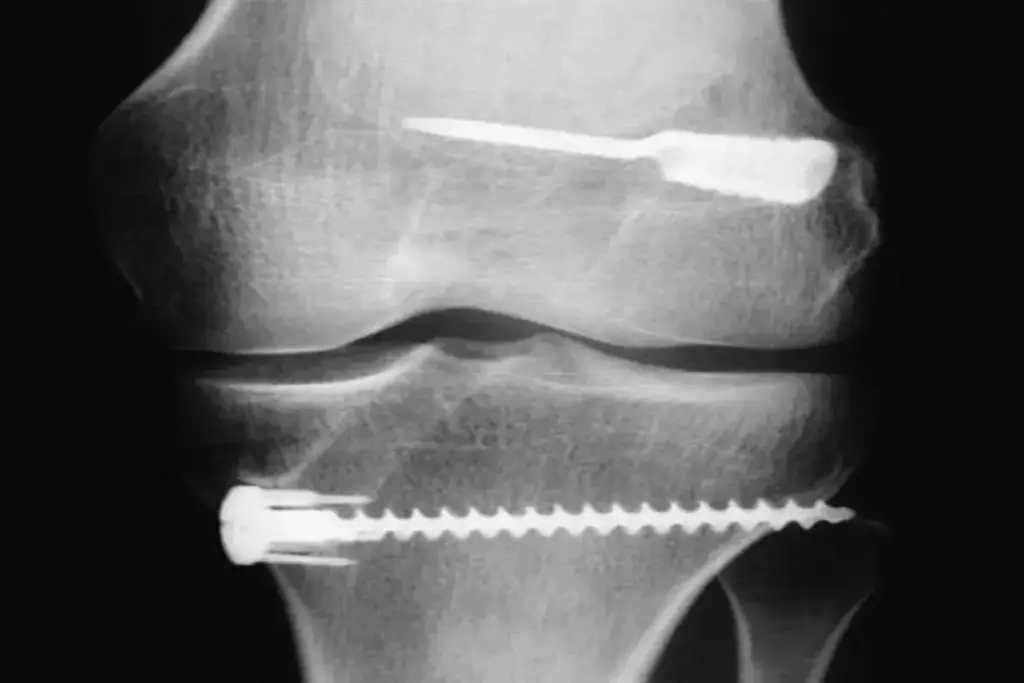

Understanding Grade 3 ACL Tears

Grade 3 ACL tears mean the ACL is completely torn. This is a big deal for knee stability. It can make the knee unstable and affect how you move and feel.

What Happens in a Complete ACL Rupture

A complete ACL rupture, or Grade 3 ACL tear, means the ligament is totally broken. This can cause:

- Instability in the knee joint

- Difficulty in performing weight-bearing activities

- Increased risk of further knee damage if left untreated or improperly managed